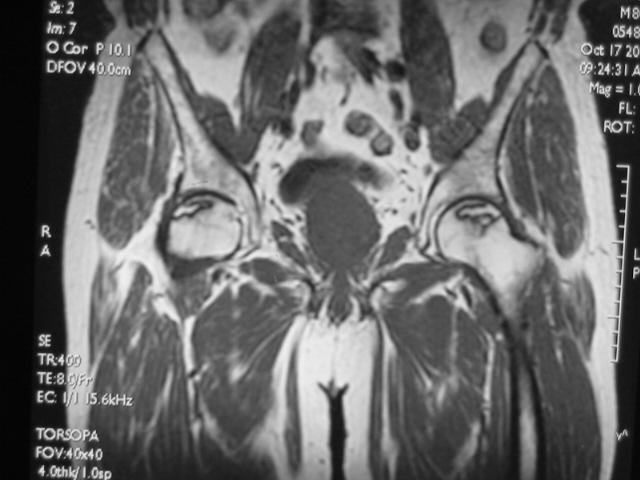

MRI诊断,俗称,核磁共振成像

正常成人股骨头的MRI表现正常成人股骨头骨髓内富含脂肪,在T1及T2加权图像上成圆形的高信号。股骨头及股骨颈表面骨皮质均为低信号。

在冠状面上,股骨头中央的承重骨小梁,表现为自外下缘到内上缘的稍低信号带。

闭合的骨骺线为横行低信号线,两端与致密骨相连。

MRI扫描技术

患者取仰卧位,扫描范围自髋臼上3cm至股骨粗隆下。

层厚5mm,层间距1mm连续扫描。

选择自旋回波SE序列T1WI、T2WI及STIR冠状面扫描,横轴位T1W扫描。